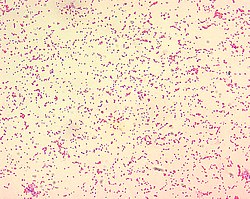

| Brucella spp. are gram-negative in their staining morphology. Brucella spp. are poorly staining, small gram-negative coccobacilli (0.5-0.7 x 0.6-1.5 µm), and are seen mostly as single cells and appearing like "fine sand". | |

Brucella abortus is a Gram-negative bacterium in the family Brucellaceae and is one of the causative agents of brucellosis. The rod-shaped pathogen is classified under the domain Bacteria.[1] The prokaryotic B. abortus is non-spore-forming, non-motile and aerobic.[2]